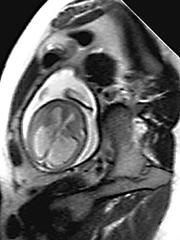

图示:20周胎儿超快磁共振成像显示明显的侧脑室扩张。CFDT

回顾了脑积水和神经管畸形的家族史。进行完整的超声波检查,以寻找其他异常情况。但是超声评估本身可能忽略重要的异常,这将影响结果。超快速胎儿磁共振成像是产前神经成像更精确的解剖学形式。射频脉冲或磁场对母亲或胎儿没有明显的危险。因此,由有经验的儿科神经放射科医师进行核磁共振扫描,排除任何额外的中枢神经系统异常。羊膜穿刺术用于病毒培养、染色体分析和甲胎蛋白水平。